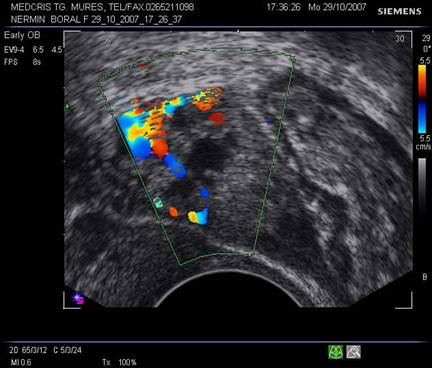

Fig nr 61 La

exam doppler color, embionul din sacul extrauterin are activitate cardiaca ( cu

sageata )